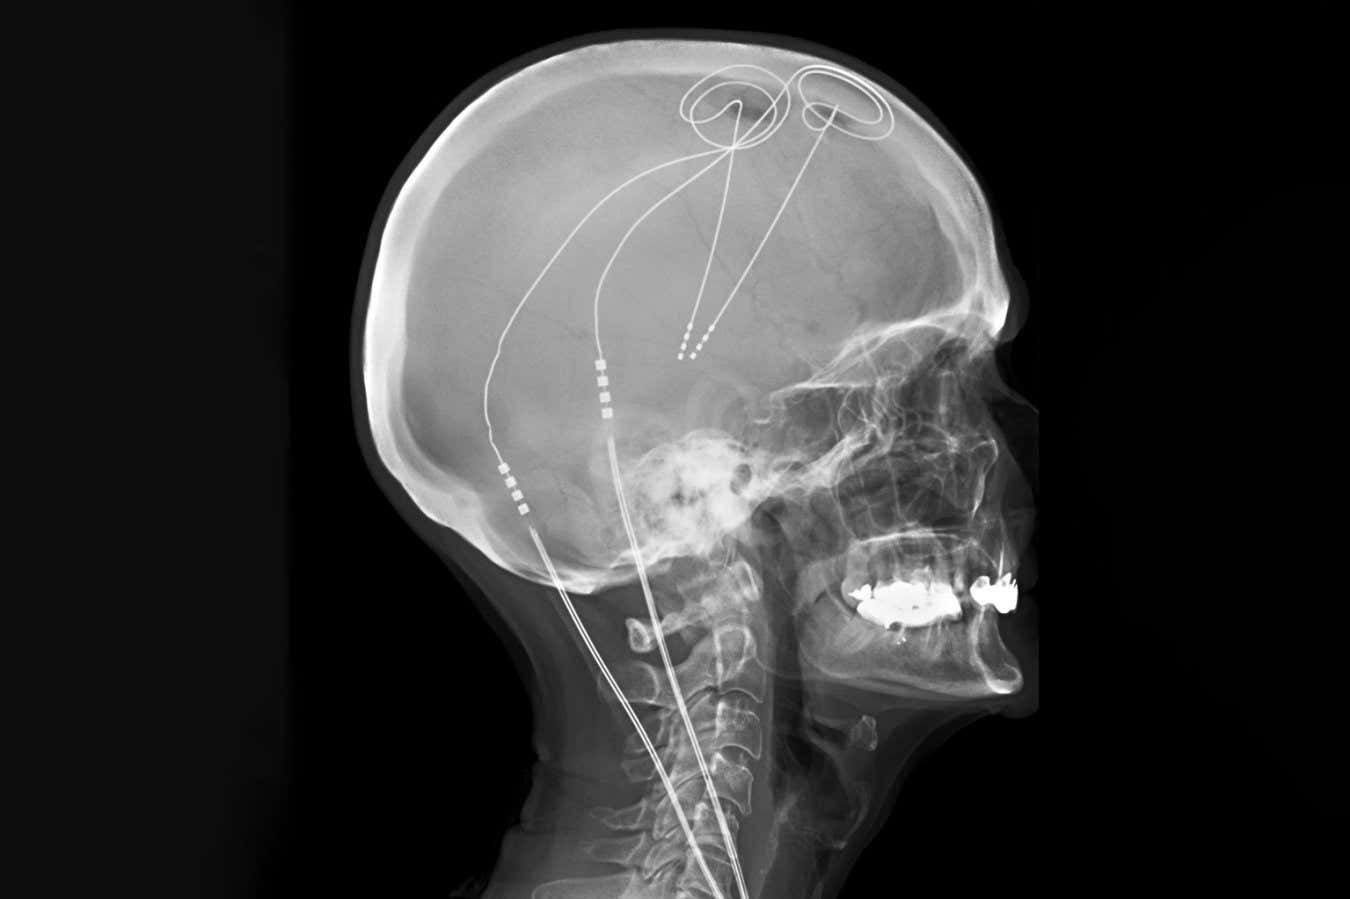

Deep brain stimulation is already utilized for Parkinson’s disease

Living Art Enterprise/Science Photo Library

Deep brain stimulation (DBS) involves using tiny electrodes to stimulate the brain, showing potential but also yielding inconsistent outcomes. The conventional method has typically applied a one-size-fits-all targeting of brain regions, despite indications that pain can stem from varying circuits in different individuals.

The research team employed machine learning to analyze and differentiate the electrical patterns associated with high and low pain levels. Consequently, they implanted permanent DBS electrodes personalized for each participant to monitor brain activity and optimize stimulation for pain detection and deactivation during sleep.